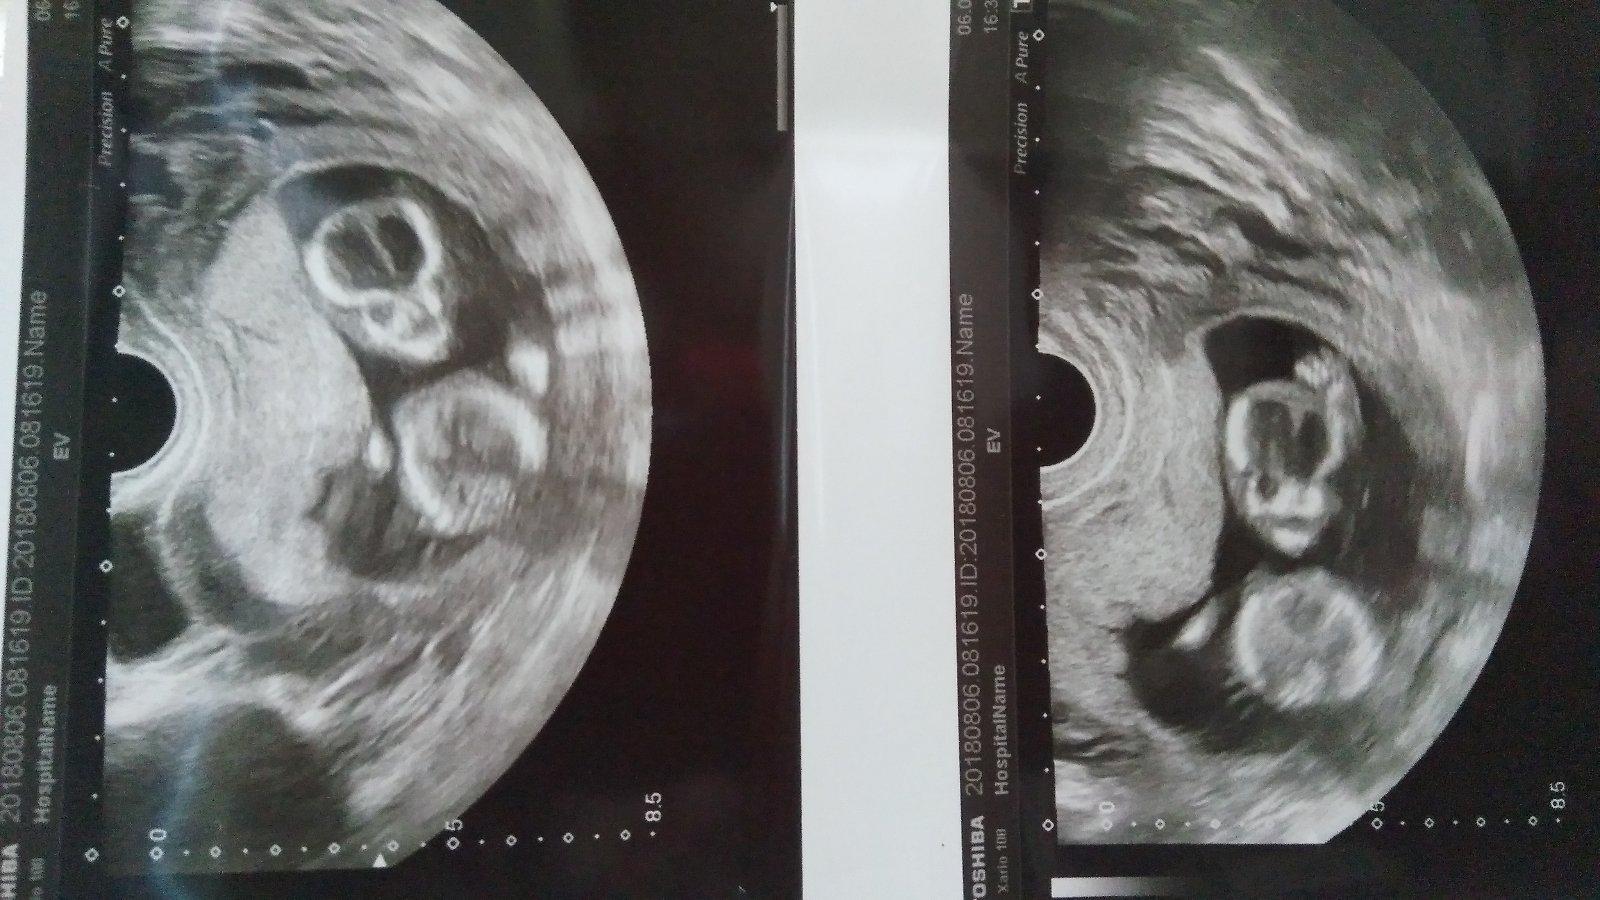

Dr. dělal ultrazvuk, snažil se kouknout na pohlaví, ale byl tam pupečník, tak rikal, ze ani nebylo nic vidět. A zase perlil. Doufám, ze tam nic nestrkate, to muzu jenom já a nikdo jiný. Miminku by se nějaký popichovani vůbec nelíbilo. Tak jsem mu řekla, ze nestrkame, ze na to nemám ani pomyšlení.

@ajdamajda mne to řekli teď při screeningu v 14tt. Ale přeci jen čekám jestli se to potvrdí kolem 20tt. Ale beru to tak na 90%. Trn doktor nám to řekl sám tak si myslím ze si byl celkem jistý jinak by nám to neříkal 🙂